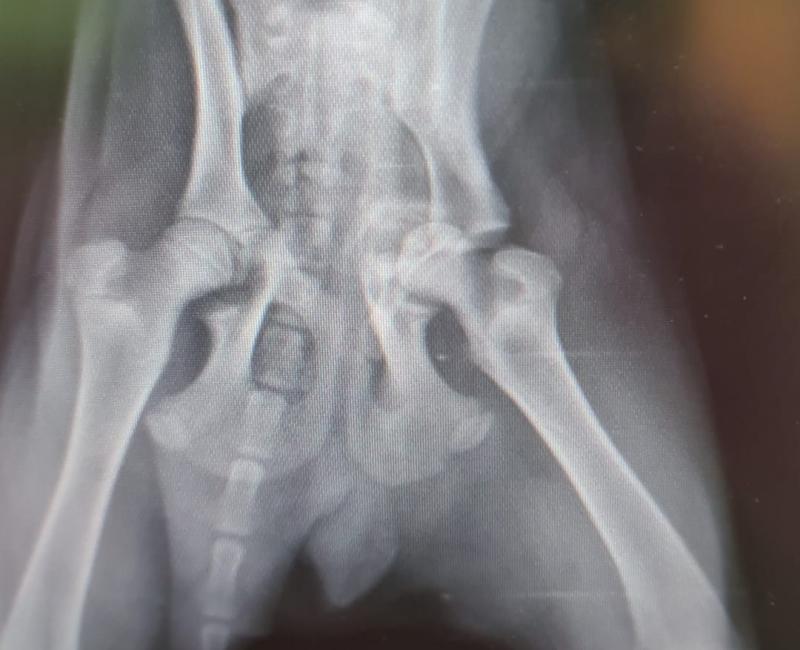

MIGAS ATROPELLADO SIN PODER LEVANTARSE.

Este precioso pequeño fue atropellado y dejado a su suerte. No podía levantarse y solo con tocarle chillaba de dolor. Cuando supimos de él no dudamos en hacer todo lo posible para ayudarle a recuperarse y que pueda tener una vida normal y feliz junto a una familia.

Hoy ha sido operado de sus fracturas de cadera y, si todo va bien, podrá volver a andar con normalidad.